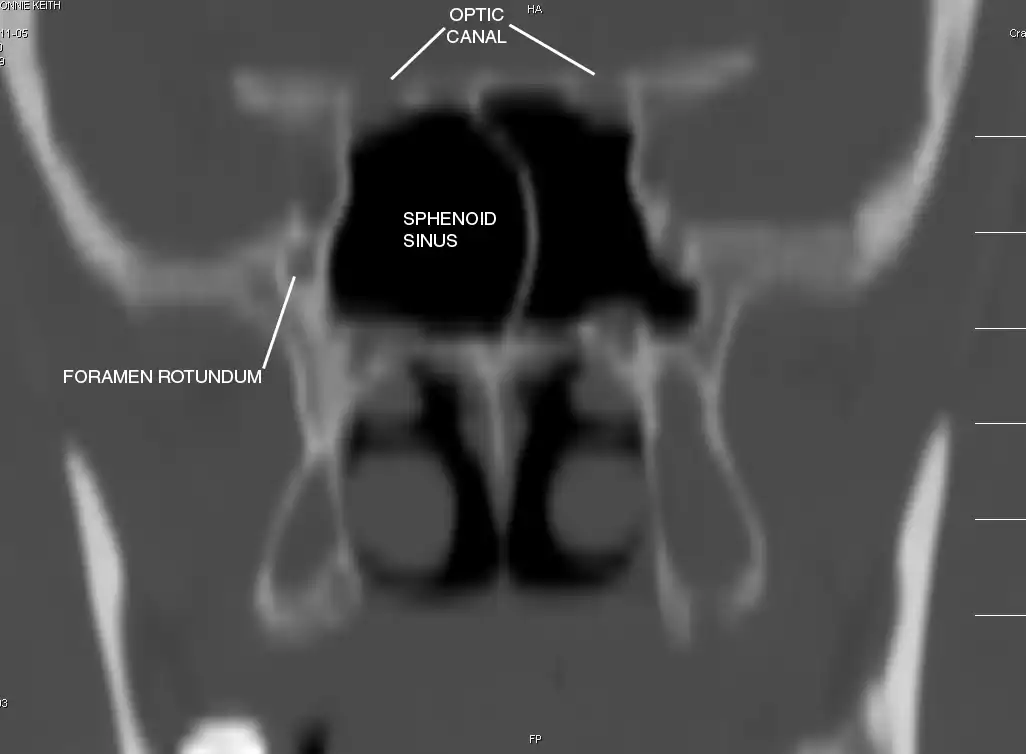

Sphenoid Sinus has 12 close structures: II, III, IV, V1, V2, VI, Vidian Nerve, Carotid artery, Brain, Dura, Pituitary.

II = Optic Nerve: 25-50% with bony dehiscence into sphenoid sinus.

V2 = Maxillary division, Trigeminal Nerve: exits foramen rotundum, superomedial to V3's foramen ovale.

C = Carotid Artery: often with bony dehiscence into sphenoid. Together with CN II forms opticocarotid recess.